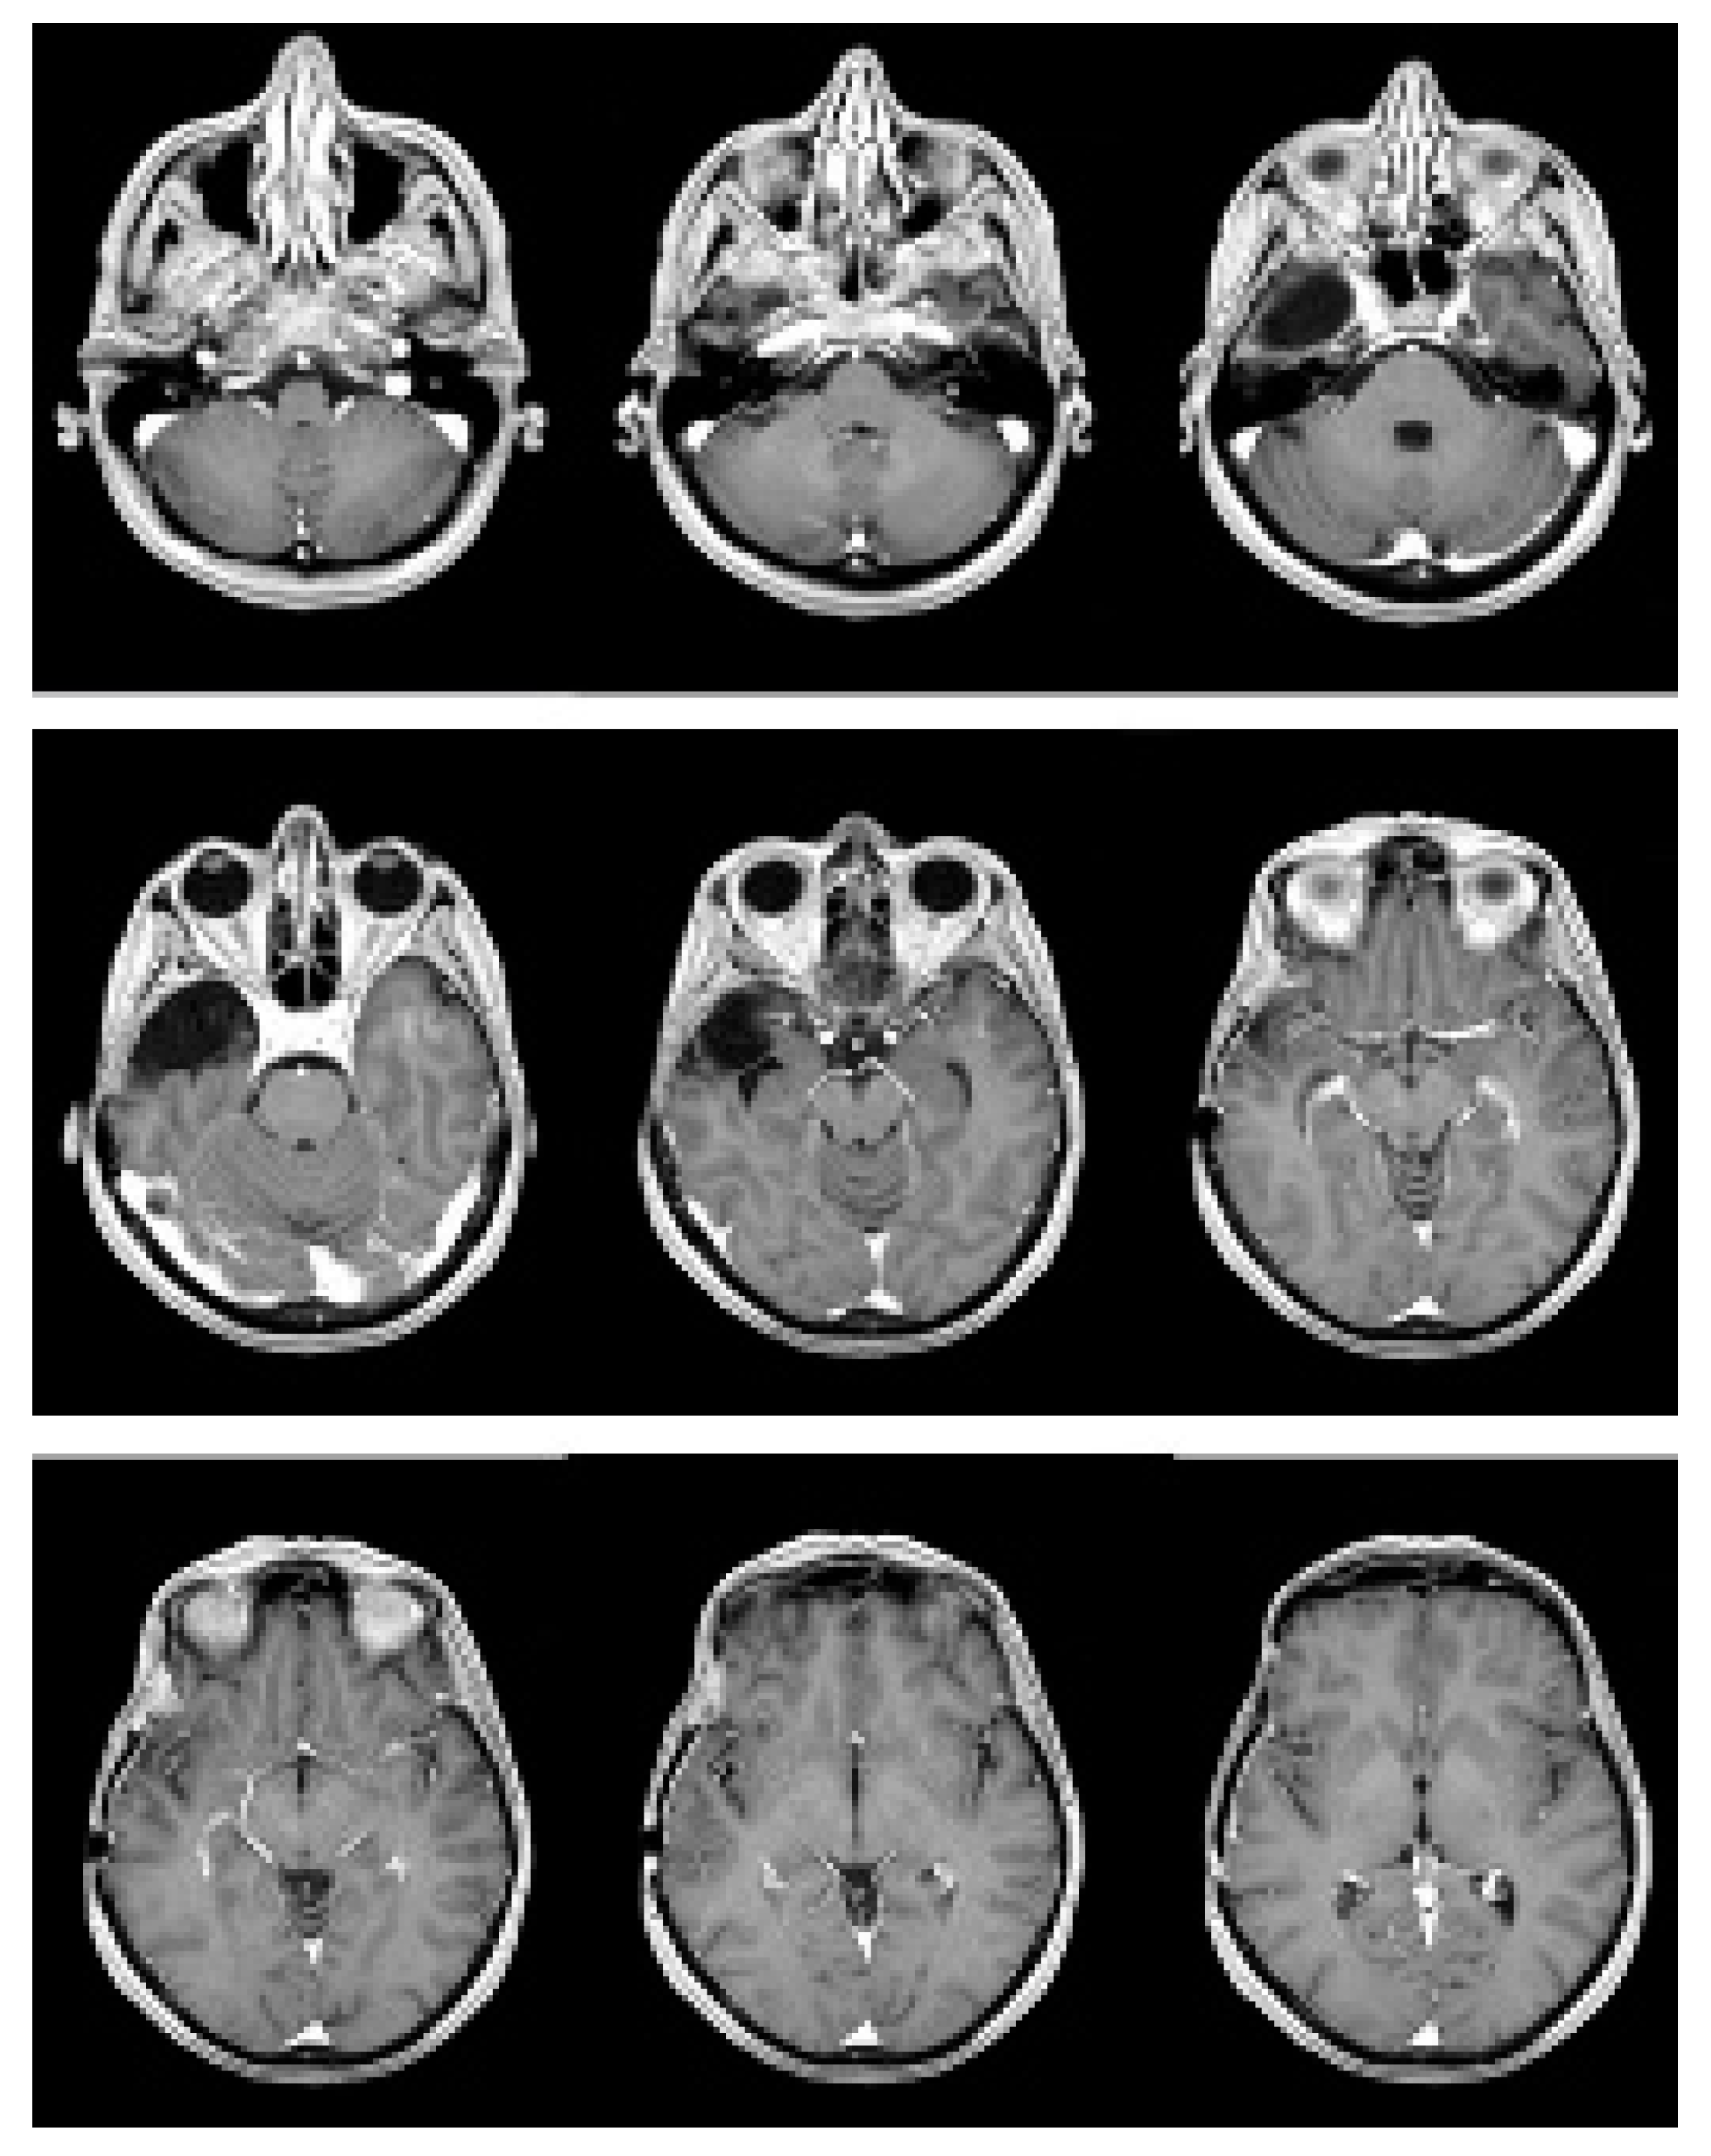

2. Case Presentation